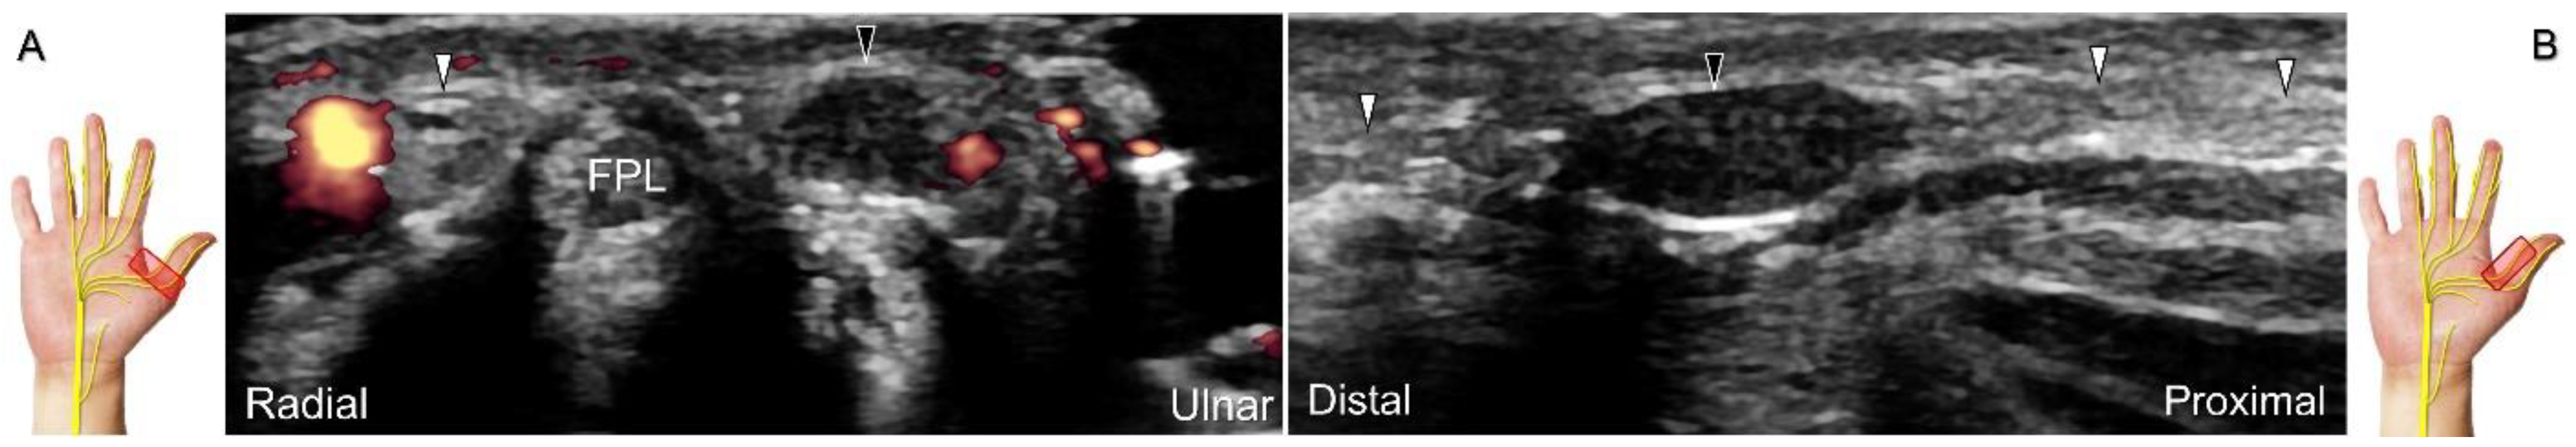

Scanning Technique

With the forearm supinated, the transducer is positioned in the axial plane at the lateral aspect of the antecubital fossa. The superficial and deep radial nerves are situated between the brachioradialis and brachialis muscles. The superficial radial nerve initially courses next to the radial artery below the brachioradialis muscle, and then departs from the radial artery in the distal third of the forearm (Figure 21A). Distally, it pierces the antebrachial fascia between the extensor carpi radialis longus and brachioradialis tendons. When tracking the terminal portion of the superficial radial nerve, the forearm can be pronated, as it courses toward the dorsal radial aspect of the wrist/hand. The superficial radial nerve travels above the proximal intersection junction between the first and second dorsal extensor compartments (Figure 21B). Later, it divides into the dorsomedial and dorsolateral branches. The former courses above the distal intersection junction of the second and third compartments (Figure 21C). The latter runs beside the extensor pollicis longus tendon (Figure 21D).

Cheiralgia paresthetica, also known as Wartenberg’s syndrome, is the compressive neuropathy of the superficial radial nerve. Symptoms such as tenderness, numbness, and allodynia can be exacerbated by wrist flexion and ulnar deviation. The nerve can be compressed by a handcuff, watch, bracelet, metal implant, ganglion cyst, or distal radius fracture. Nerve entrapment commonly takes place at the proximal intersection zone pertaining to the first and second extensor compartments (Figure 22).

Additionally, acupuncture and cannulation of the cephalic vein over the distal forearm can lead to nerve injury. To prevent iatrogenic injury, the superficial radial nerve before injection should also be recognized for de Quervain’s syndrome (Figure 23A) [44], ganglion cyst aspiration (Figure 23B), and catheterization (Figure 24A–C). For injection of the superficial radial nerve, an in-plane approach in the nerve’s short axis is preferred (Figure 24D).

Figure 21. Sonographic imaging (short-axis view) of the superficial radial nerve from the distal third of the supinated forearm (A). With the pronated forearm, the nerve is seen to travel above the proximal intersection junction (B), divide into the dorsomedial branch coursing above the distal intersection junction (C), and the dorsolateral branch running beside the extensor pollicis longus tendon (D). Arrowheads: superficial radial nerve; white arrow: dorsomedial branch; black arrow: dorsolateral branch. RA: radial artery; APL: abductor pollicis longus tendon; EPB: extensor pollicis brevis tendon; ECRL: extensor carpi radialis longus tendon; ECRB: extensor carpi radialis brevis tendon; EPL: extensor pollicis longus tendon; C: cephalic vein.

Figure 22. Sonographic imaging (short-axis view) of the dorsolateral branch of the superficial radial nerve at normal (A), swollen (B), and compressed (C) segments. White arrowhead: normal segment; black arrowhead: swollen segment; orange arrowhead: entrapped segment. ECRL: extensor carpi radialis longus tendon; ECRB: extensor carpi radialis brevis tendon; EPL: extensor pollicis longus tendon.

Figure 23. Sonographic imaging of the superficial radial nerve beside the first extensor compartment of the wrist (A), and a ganglion cyst over the second extensor compartment of the wrist (B). White arrowheads: superficial radial nerve; white arrow: needle. APL: abductor pollicis longus tendon; EPB: extensor pollicis brevis tendon; ECRL: extensor carpi radialis longus tendon; ECRB: extensor carpi radialis brevis tendon.